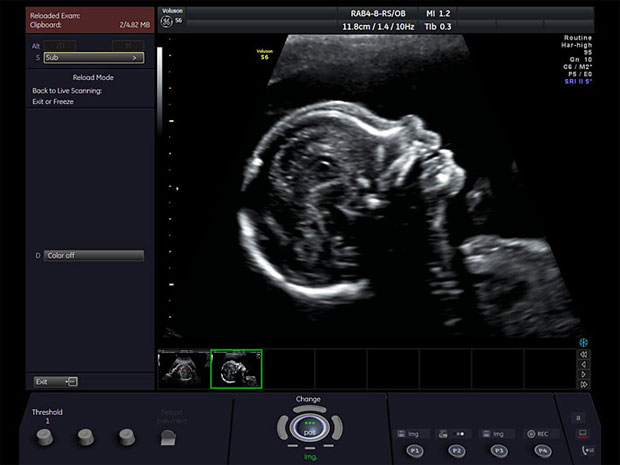

La ecografía es un procedimiento indoloro e inocuo, en el que no se utilizan radiaciones perjudiciales para la madre o el feto, y que permite diagnosticar patologías uterinas, ováricas, mamarias y fetales.